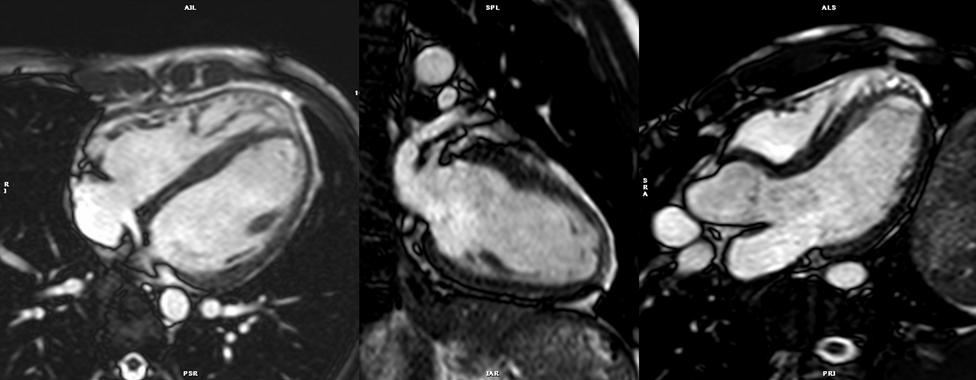

3. bSSFP左室短軸像シネMRI(Fig. 3

• 左室や右室の駆出率など心機能計測に用いる,非常に重要な撮影である.左室心基部から心尖部までを含める.スライス厚は,6~8 mm,ギャップ2~4 mm(全体で10 mmとなるように設定).壁運動の評価を最適化するためにシネMRI各時相間の時間分解能<45 msecとする.呼吸停止下で撮像するのが理想的.呼気時の呼吸停止のほうが安定した体位を得やすいが,患者によっては吸気時の呼吸停止のほうが楽という場合があり,その際には吸気で撮影する.左室短軸断面は二腔長軸像および四腔長軸像のスカウト像を用いて決定する.この断面は長軸像の左室中央部と直交するスライスとなる.長軸方向の壁運動と血液の流入が描出される必要があるためシングルショットMRIよりシネMRIが望ましい.

Pediatric Cardiology and Cardiac Surgery 40(4): 260-271 (2024)

Fig. 3 Top: Planning of the short axis image plane parallel to the mitral valve in the 4 chamber long axis plane (left) and 2 chamber long-axis plane (right). Bottom: 18 short axis cine slices shown from base (top left) to apex (bottom right).

シネMRIの撮影の項で記載したように,左室長軸に沿って心臓全体を連続する単軸像で撮影し評価する(Fig. 3).